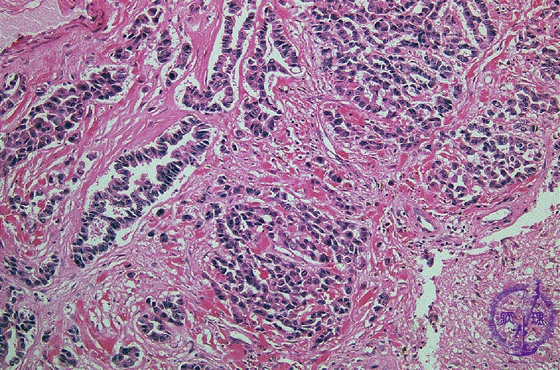

- (10)Metastatic brain tumor

Microscopic findings (H.E. high magnification): Tumor cells showed apparent glandular structures (arrows), indicating the brain metastasis of adenocarcinoma (from lung).